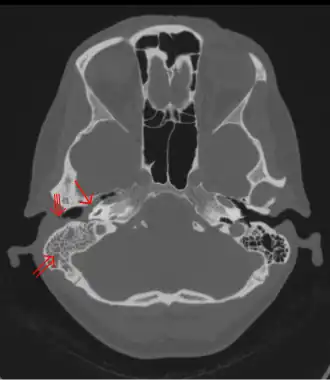

The diagnosis of mastoiditis is clinical—based on the medical history and physical examination. Imaging studies provide additional information; The standard method of diagnosis is via MRI scan although a CT scan is a common alternative as it gives a clearer and more useful image to see how close the damage may have gotten to the brain and facial nerves. Planar (2-D) X-rays are not as useful. If there is drainage, it is often sent for culture, although this will often be negative if the patient has begun taking antibiotics. Exploratory surgery is often used as a last resort method of diagnosis to see the mastoid and surrounding areas.[2][9]